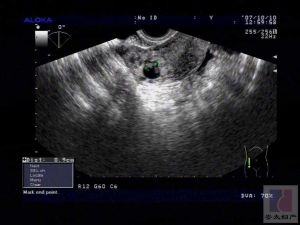

3.B型超音波檢查

可見子宮增大,宮腔內出現彌散分布的雜亂光點反射,但無妊娠囊光環。腹腔內可見胎兒及胎盤反射波。但有時,除子宮和胎頭外,其他結構不易辨認。X線檢查顯示:胎兒影像清晰度增加,而胎兒周圍的子宮軟組織陰影消失;胎兒貼近母體腹壁,位置較高,胎位異常多見。

3.妊娠只存在於腹腔內,無輸卵管妊娠等的可能性。B型超聲顯象若宮腔空虛,胎兒位於子宮以外,有助於診斷。